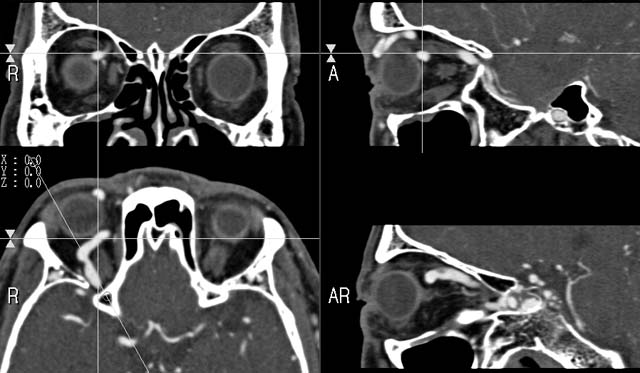

MPR

Data acquired by M. Nakane M.D., processed by K. Katada M.D.